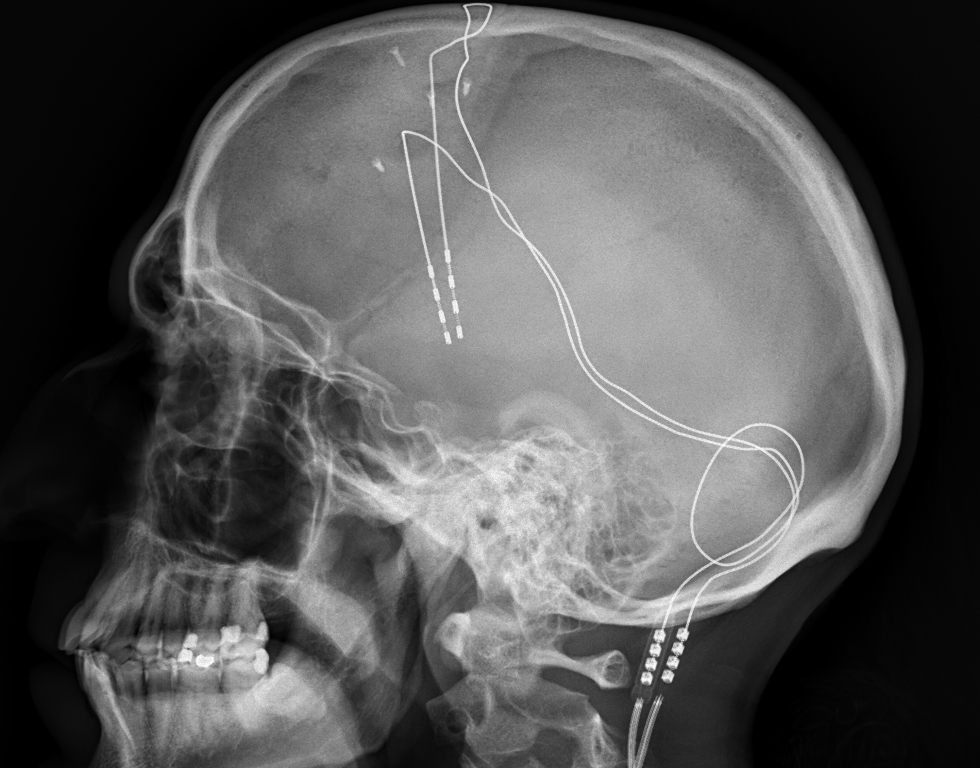

Identifying Centers of Depression Using Deep Brain Stimulation

Studies with deep brain stimulation may provide a way to personalize treatment for depression, where one would have to map out brain areas that are susceptible to depression or may be related to depression. This approach may be individualized to each patient.

With that said, a Deep Brain Stimulation case study suggests that the ventral striatum may be associated with depression.